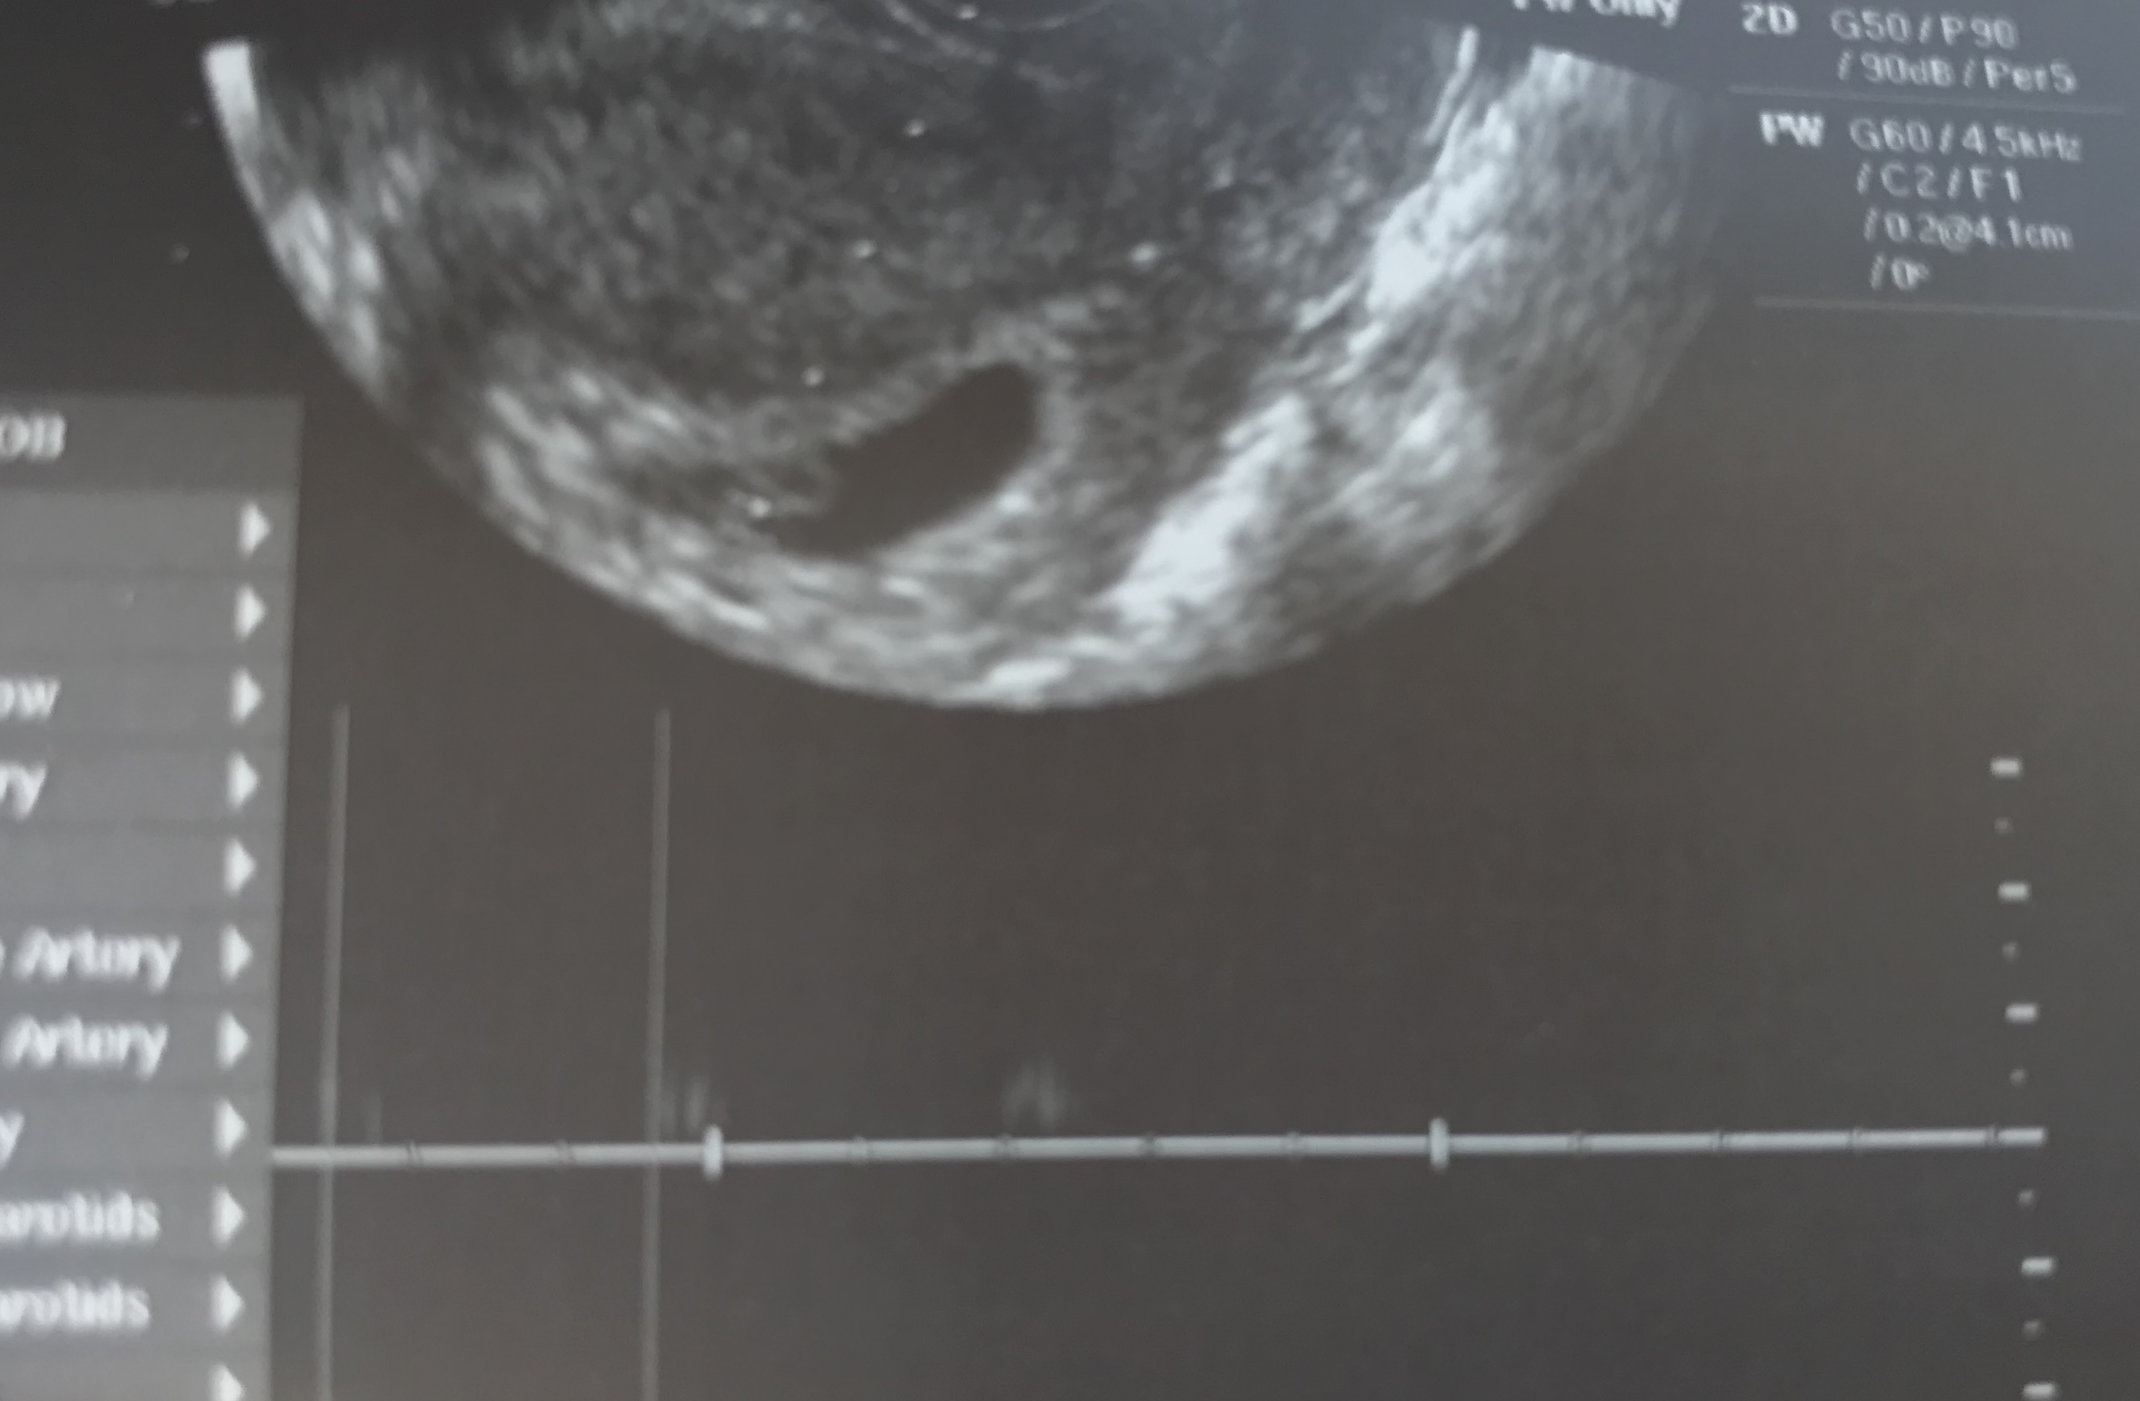

First u/s today at 6w4d. Honestly this early it’s just all blobs to me but my dr diligently showed us the flutter of the HB and also had us listen. I think HB was clocked at 138. Here’s the pic with sound waves. I think the print out said measuring 6w1d but my dr said the embryo was measuring at .4 cm and anything between .25 and .5 would be just right.